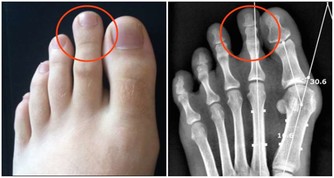

4、痛風石

夏季是痛風“高發期”! 做對5件事,痛風遠離你!

痛風石的形成是長期高尿酸血症引起的組織損傷的結果,是痛風的特徵性病變;沉積在關節囊,影響關節活動;可導致骨“鑿孔”樣損害,嚴重者可導致骨折。關節脫位及畸形;痛風石破潰後,不易癒合,極易導致截肢悲劇。